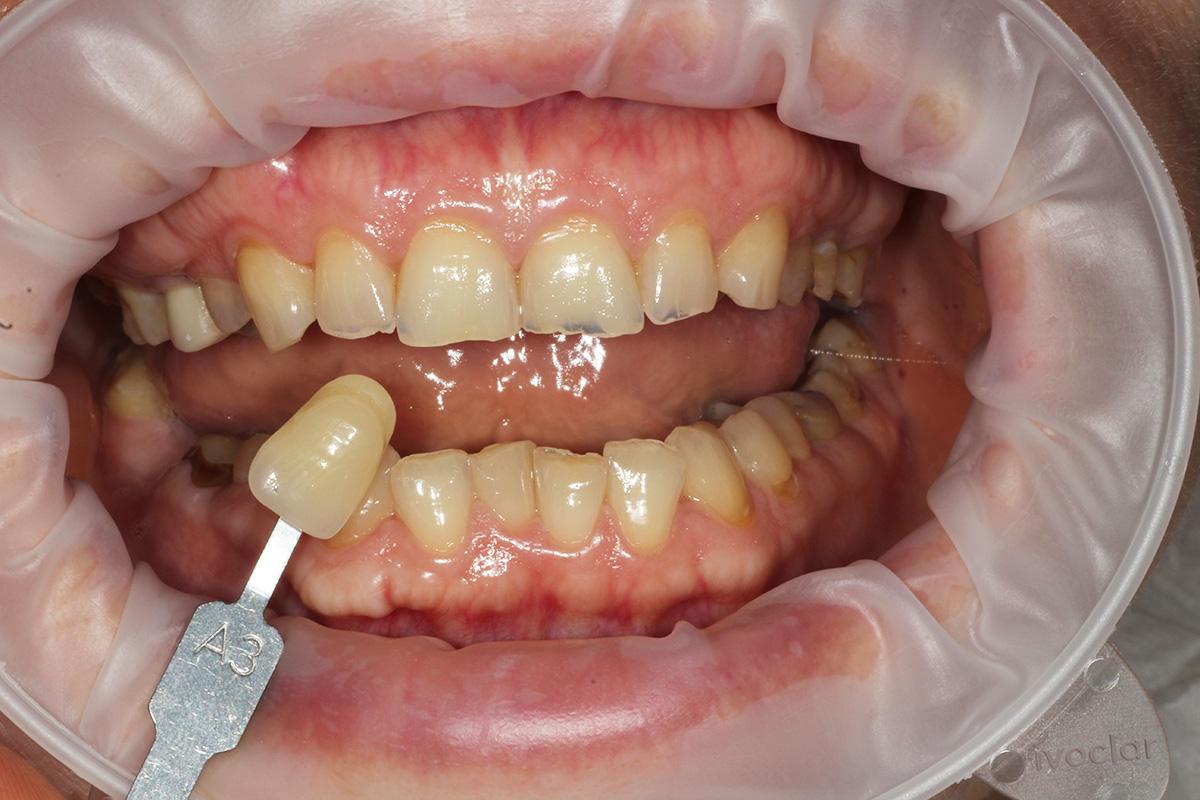

Pacjentka, zgłaszając się już na kolejną wizytę świadomie podjęła opcję pośrednią z proponowanych działań: wyleczenie zębów zachowawczo, endodontycznie z zabezpieczeniem protetycznym, estetyczne korekty uśmiechu licówkami, ćwierćkoronami i koronami, jednak bez pełnej przebudowy zwarcia (z zachowaniem starszych odbudów w strefach bocznych, które były wykonane na implantach w przeszłości), która jest zawsze najbardziej polecana, odtwarza prawidłowe kontakty, a także umożliwia lekarzowi i technikowi najlepsze warunki do nadania odpowiednich i harmonijnych kształtów. Te wszystkie działania chronią na przyszłość staw skroniowo-żuchwowy.

Pomimo zaleceń dr do wdrożenia również leczenia ortodontycznego, Pacjentka, znając wszystkie wady i zalety bezwzględnie zdecydowana zakamuflować stłoczenia, nieprawidłowości kontaktów, płaszczyzny zgryzowe, tylko i wyłącznie protetycznymi rozwiązaniami. Dr Joanna ustaliła z Pacjentką pod Jej wymagania wspólny plan działań. Wybierając takie rozwiązanie lekarz i laboratorium ma zawsze utrudnienie, by jaknajbardziej harmonijnie zaplanować projekt uśmiechu.